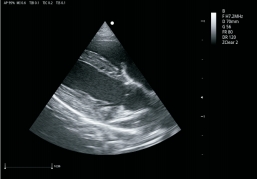

VU3移植了uSeed高端成像技术和图像算法,高度集成化的硬件设计,将优异的图像、 全面的功能、高效的工作流、便捷的移动性集于一身,实现一机两用(台式/便携式)。

卓越的图像质量